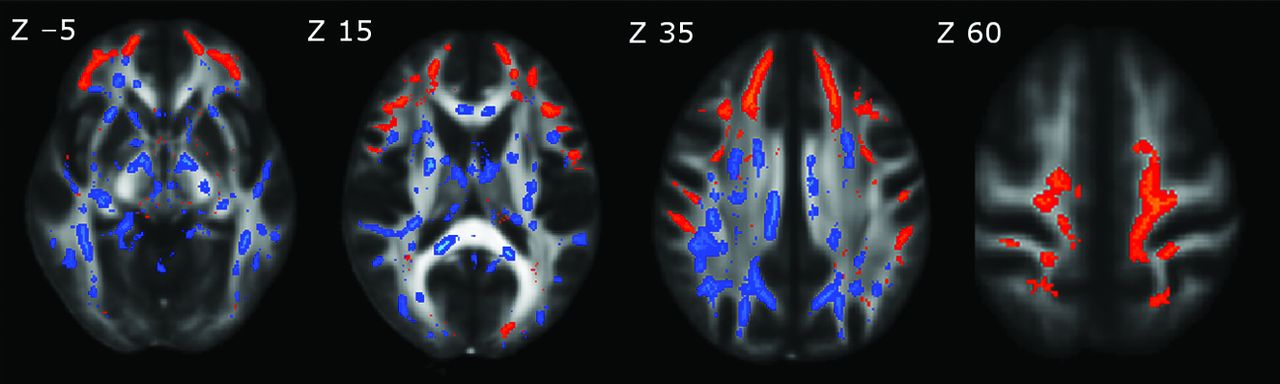

Voxelwise TBSS analyses revealed widespread alterations in multiple DTI indices (Fig 1). Compared with the healthy group, patients with pHSP showed decreases of FA (P < .05, corrected) in multiple WM regions (Fig 1A), including the bilateral anterior thalamic radiations, corticospinal tracts, corpus callosum with forceps major and minor, and parts of the inferior and superior longitudinal fasciculi. Significant clusters for each matrix were separately masked and labeled with reference to the JHU ICBM-DTI-81 White Matter Labels, part of the FSL atlas tools (Table 2). Most regions showing a decrease in FA showed a corresponding increase in RD (P < .05, corrected, Fig 1C). Changes in MD (P < .05, corrected, Fig 1B) were more restricted in comparison with regions of decreased FA and increased RD. No significant differences emerged after voxelwise TBSS analysis of AD.

DTI indices maps (P < .05, corrected) are represented in the FMRIB58_FA template on the axial plan with z-axis coordinates (in millimeters) above the upper row images. Green corresponds to the mean white matter skeleton of all participants. A, Red-yellow represents decreased FA. B, Pink-light pink represents increased MD. C, Blue-light blue represents increased RD.

Percentage changes of the voxels in the WM skeleton that passed the significance threshold (P < .05, corrected) were 51%, 41.6%, and 11.9%, respectively, for RD, FA, and MD clusters. All clusters consisted of a large number of voxels that did not split into smaller clusters even after increasing the significance threshold to P < .01. All cluster characteristics are detailed in the supplementary material (On-line Table 2).